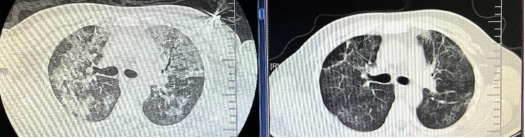

患者为47岁男性,醉酒后外伤导致下颌骨体部断裂、上颌骨牙槽骨折、鼻骨舌骨骨折,因误吸导致心跳呼吸骤停,北京口腔医院立即行心肺复苏、紧急气管切开、呼吸机辅助通气、血管活性药物泵入维持血压,3分钟后恢复自主循环。口腔医院第一时间启动院际转诊机制,转入我院呼吸与危重症监护室时双肺均呈"白肺"表现,血气分析提示严重呼吸衰竭,氧合指数PaO2/FiO2<100(氧合指数为肺脏将吸入的氧气转化为动脉血中氧气的能力,正常值为400-500mmHg),呼吸团队迅速完善支气管肺泡灌洗,病原学结果提示多重耐药菌肺炎(金黄色葡萄球菌+屎肠球菌+肺炎克雷伯菌),予美罗培南+万古霉素精准抗感染、有创呼吸机辅助通气维持氧合。经积极治疗后,患者痰量减少,炎症指标显著下降,但仍高热,血氧饱和度改善不明显,复查胸CT考虑感染后机化,在病程第8天果断加用甲强尼龙进行免疫调节,逆转肺纤维化进程。历经13天治疗,患者肺部病灶显著吸收(CT复查渗出减少80%),成功撤离呼吸机并封堵气切套管,最终安全转回北京口腔医院完成颌骨重建手术,恢复良好。